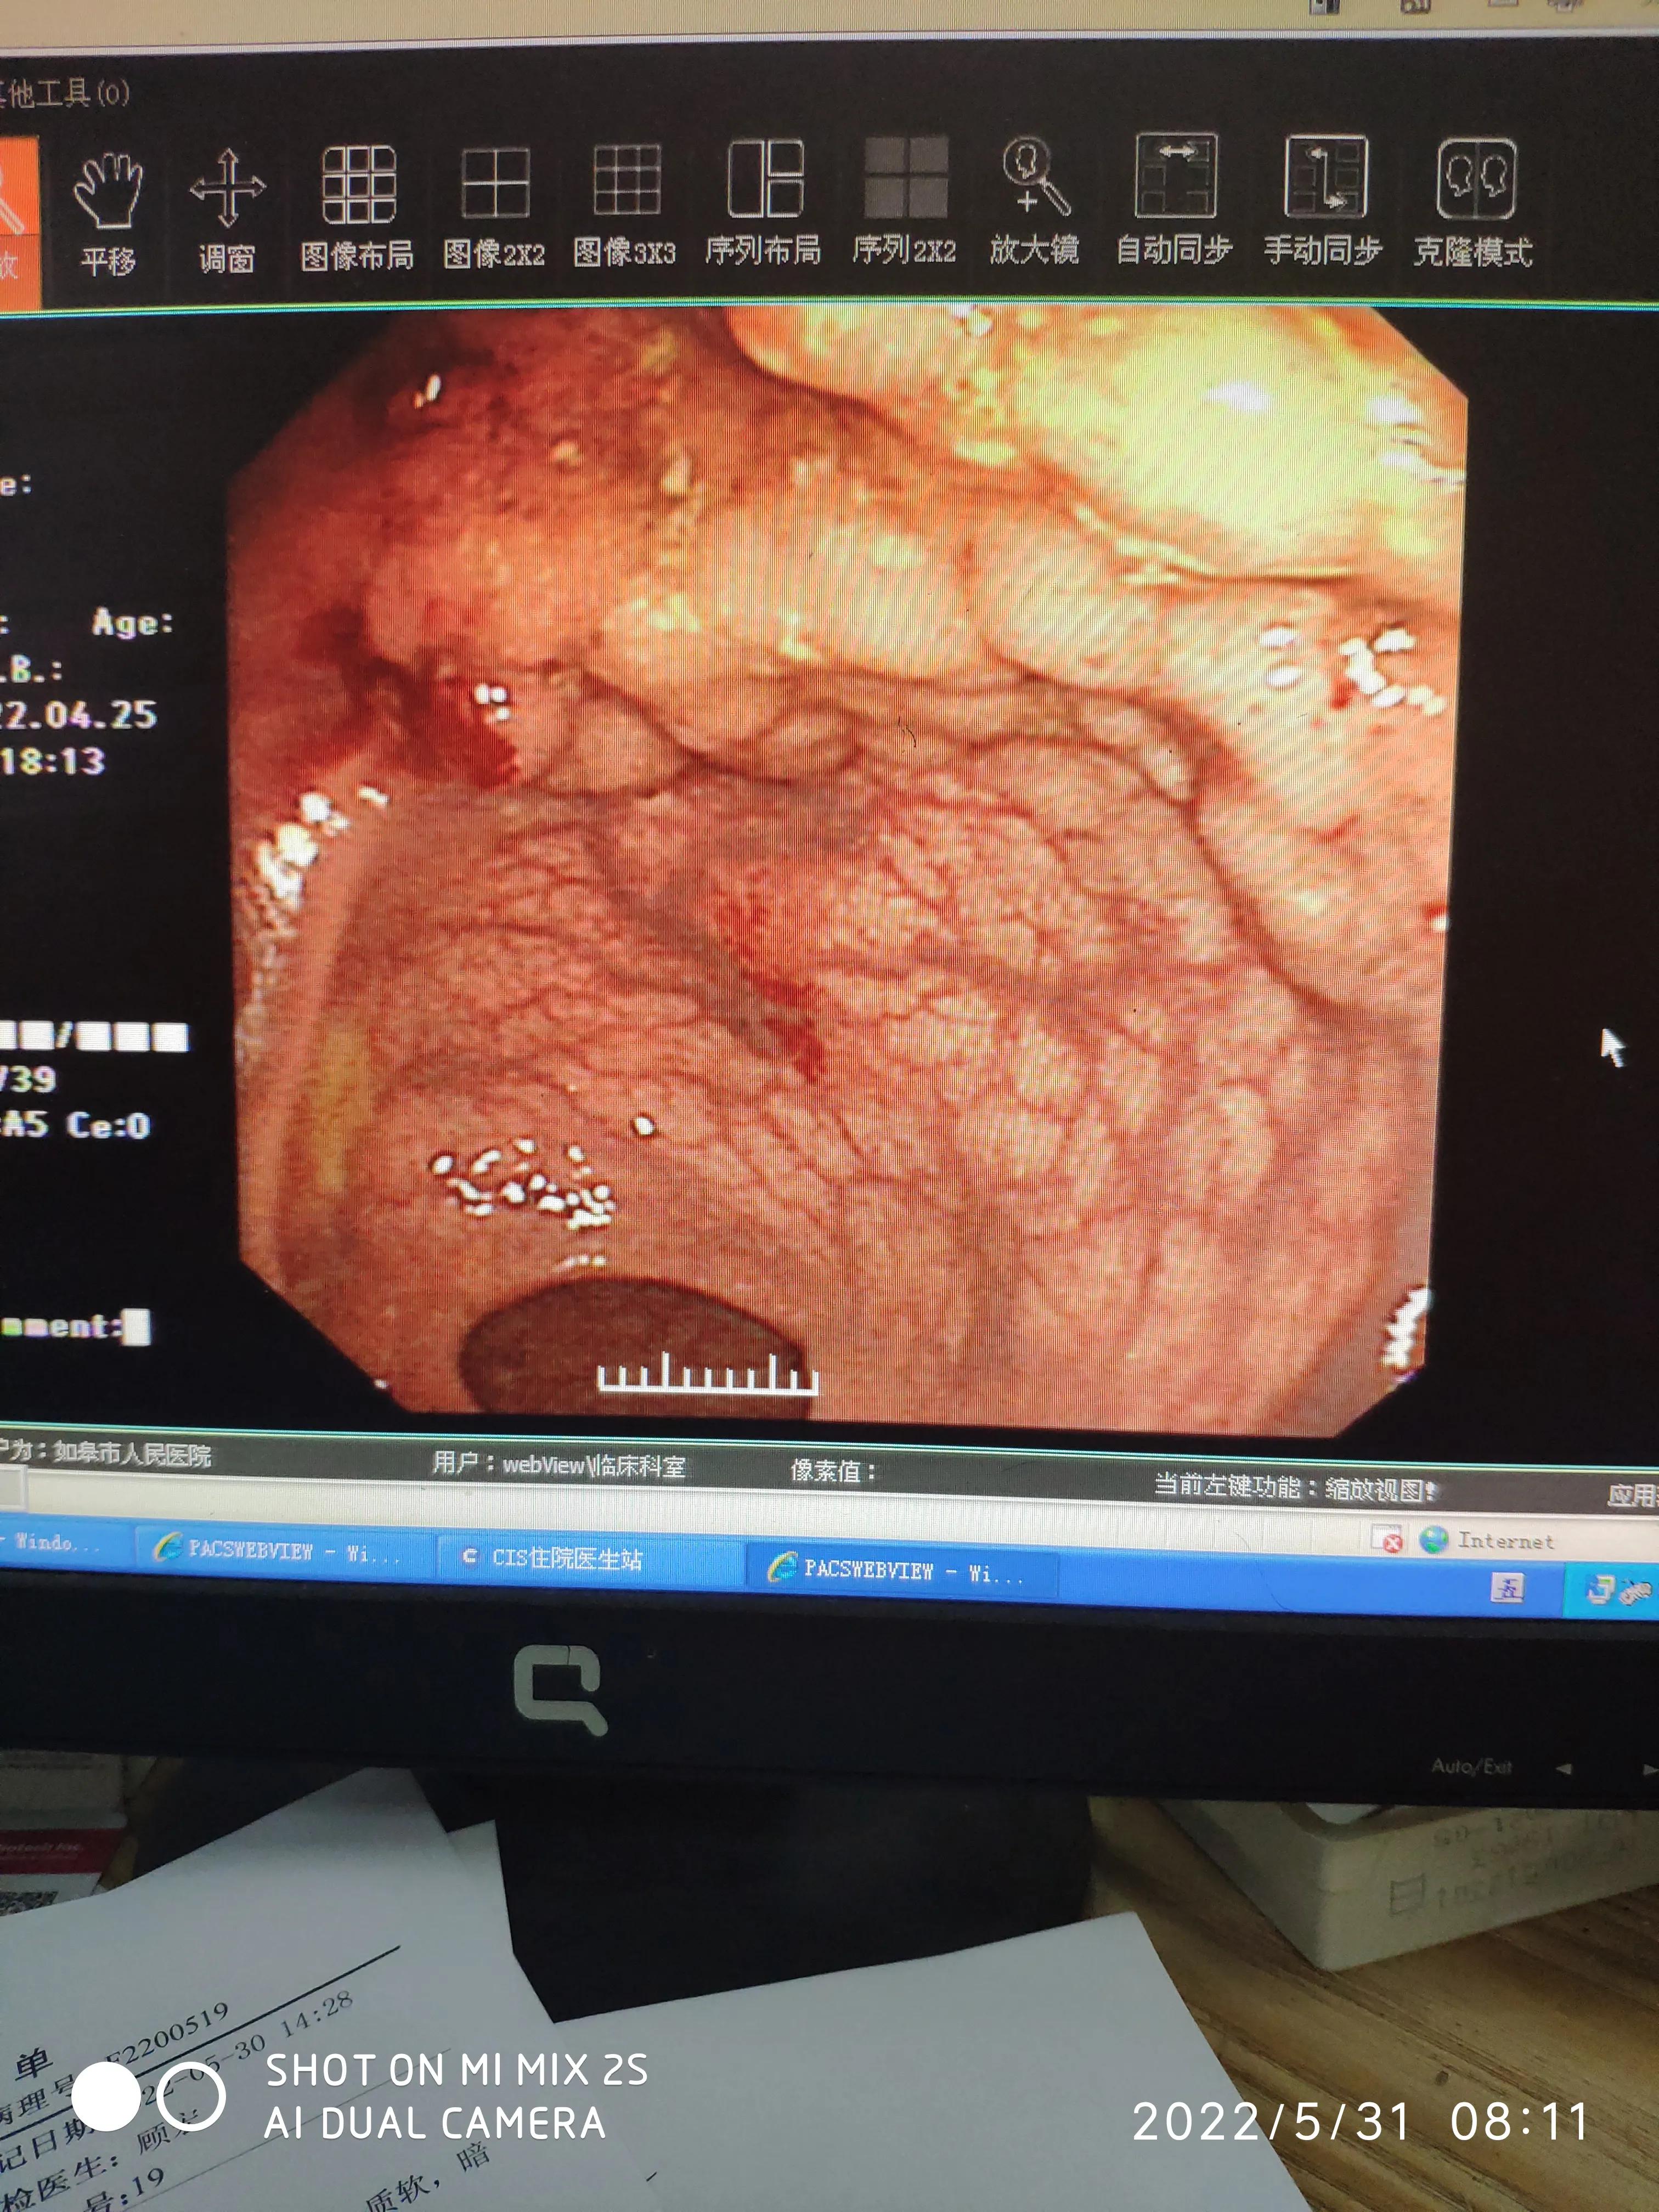

入院当日即进行了各项术前检查与肠道准备。第二天,在手术室进行了内镜下直肠病灶切除术:直肠可见7.5cm*6cm侧向发育性肿瘤,中央见大结节,予以黏膜下注射美兰+肾上腺素+甘油果糖抬举病灶,切开刀预切开病灶边缘,建立隧道,逐步完整大块剥离病灶,热钳处理创面,钛夹缩小创面。(术前术后镜下下图)

ESD切除后肠镜下改变